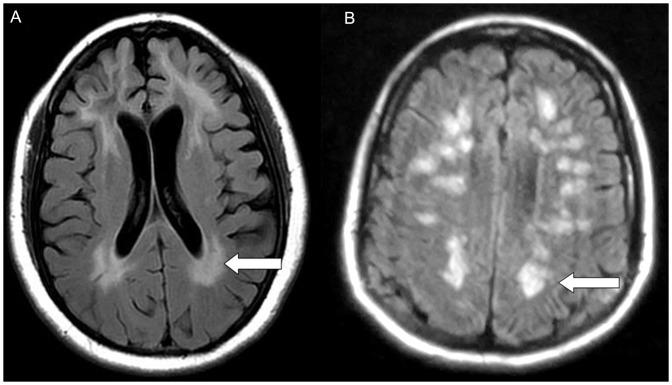

Hashimoto's encephalopathy and mild Alzheimer's disease showed cognitive impairments in episodic memory, attention, executive function and visuospatial ability, but naming ability was unaffected in Hashimoto's encephalopathy. The MRI of Hashimoto's encephalopathy showed leukoencephalopathy-like type or limbic encephalitis-like type; the lesions did not affect the temporal cortex which plays a role in naming ability.

Except that the naming ability was retained, the impairments in cognitive functions for the Hashimoto's encephalopathy patients were similar to those of Alzheimer's disease patients. These results were consistent with the MRI findings.